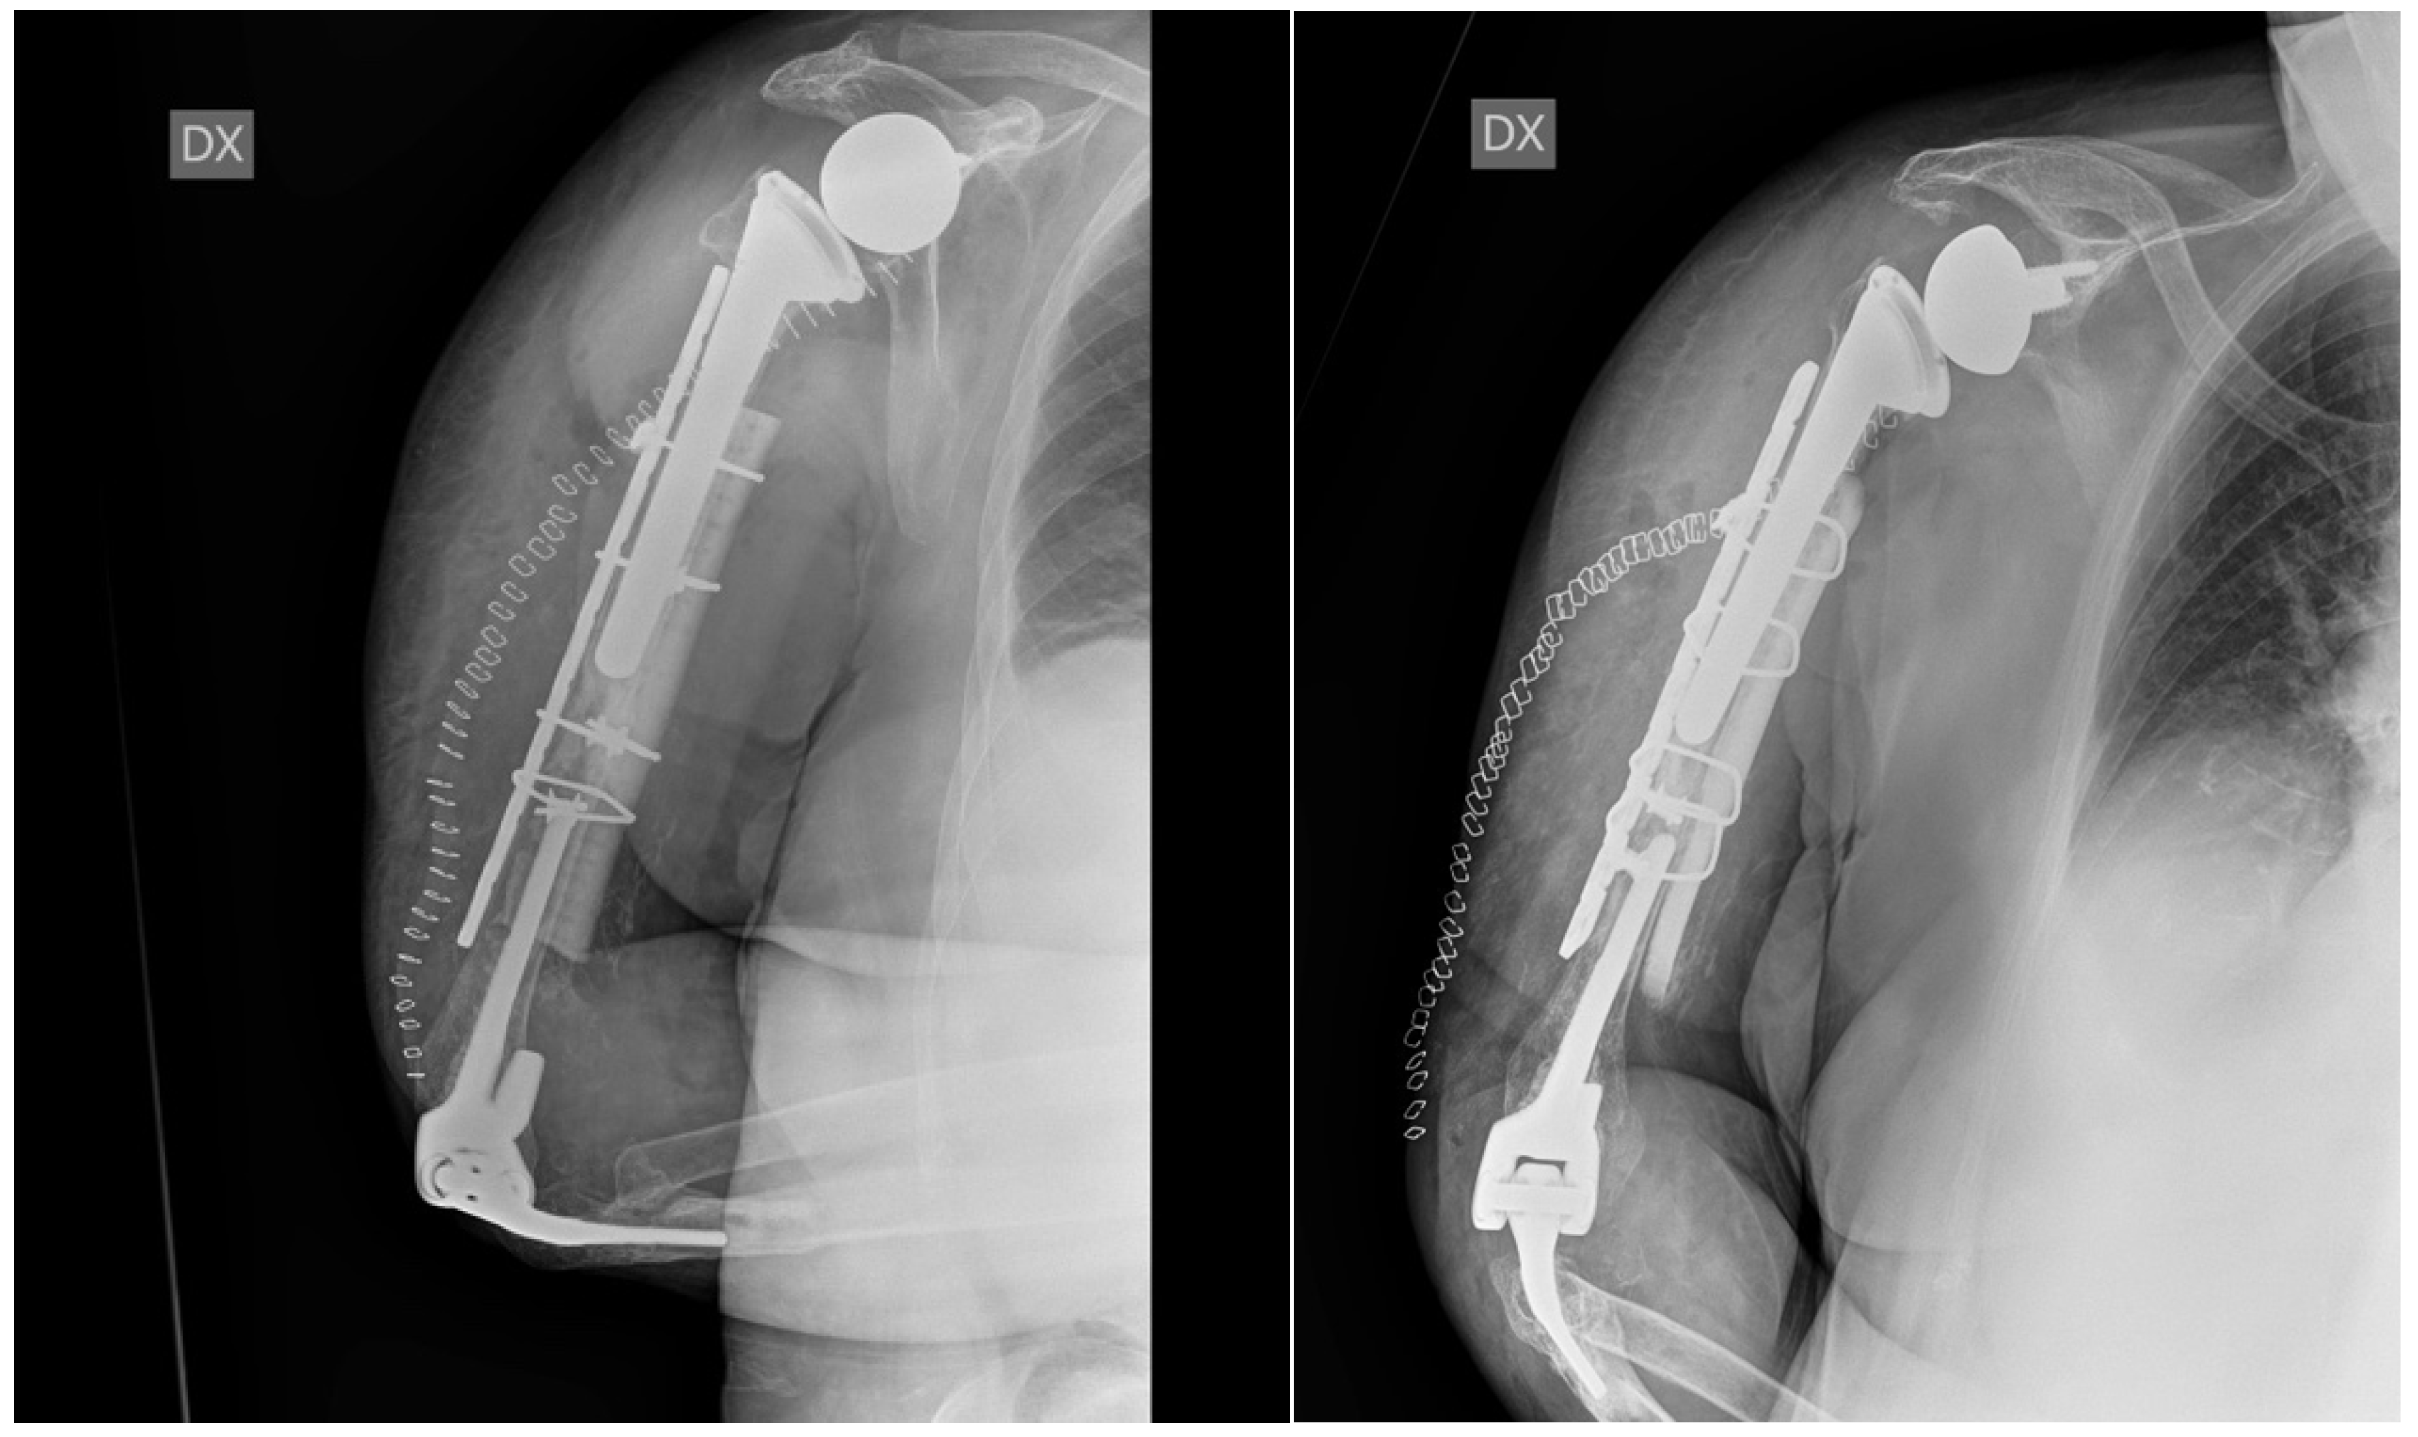

The rehabilitation program included 30 days of shoulder immobilisation whilst keeping a Gilchrist bandage. Only the active mobilisation of the elbow was encouraged from the first postoperative day. Magnetic field therapy (Biostim, IGEA Clinical Biophysics) was also prescribed in order to improve and speed up the bone healing process. A full range of motion (without restrictions) was allowed after 30 days of radiological and clinical follow-up, but muscle strengthening against resistance was forbidden at the time and was gently allowed at 3 months after surgery. A periodical clinical and radiological follow-up was carried out each month in the first trimester and then every three months up to a year. At 6 months of follow-up, the wound was well-healed, and the range of motion was gradually improving. The check X-ray showed a good level of bone healing with the stability of metalwork and implants. The radiological healing was achieved at 9 months post-op. The X-rays at 9 months post-op showed good alignment and complete integration of the graft strut. The clinical and functional results were satisfactory both for the elbow and the shoulder (Figure 4). At the last follow-up, the DASH score was 75, the NRS (numerical rate score) was 2, the shoulder arc of motion was 100° in elevation, the external rotation was 5°, and the internal rotation was toward the gluteus, and the elbow arc of motion was in ex/flex 30–110 and 50–45 in prono-supination. At 1 year follow-up, the check X-ray was again satisfactory, with no reported issues. The clinical findings were similar to those reported at 9 months of follow-up. The patient is satisfied with the postoperative course, and her expectations were met.

Figure 4.

Radiological and clinical follow at 9 months post-op: (a,b) the X-rays show stability of the fixation metalwork and of the shoulder and elbow prosthesis, good bone healing process, and good strut integration; (c–e) satisfactory shoulder range of motion; no scare issues.

The reported outcomes are really different and contradictory among the articles included in our review. Mavrogenis reported a return to ADL (activity daily living) in 10 months [14], while Kieser et al. [9] reported a DASH score of 54.2 at 1 year, and LeBlanc and DeFroda reported only the elbow range of motion [11,13]. Our patient is now regularly followed up, with satisfactory radiological and clinical outcomes. The X-rays at 9 months post-op showed good alignment and complete integration of the graft strut. The clinical and functional results were satisfactory both for the elbow and the shoulder (Figure 4). At the last follow-up, the DASH score was 75, the NRS was 2, the shoulder arc of motion was 100° in elevation, the external rotation was 5°, the internal rotation was toward the gluteus, and the elbow arc of motion was in ex/flex 10–110 and 50–45 in prono-supination. These can objectively be considered very good final results, considering the previously reported cases.